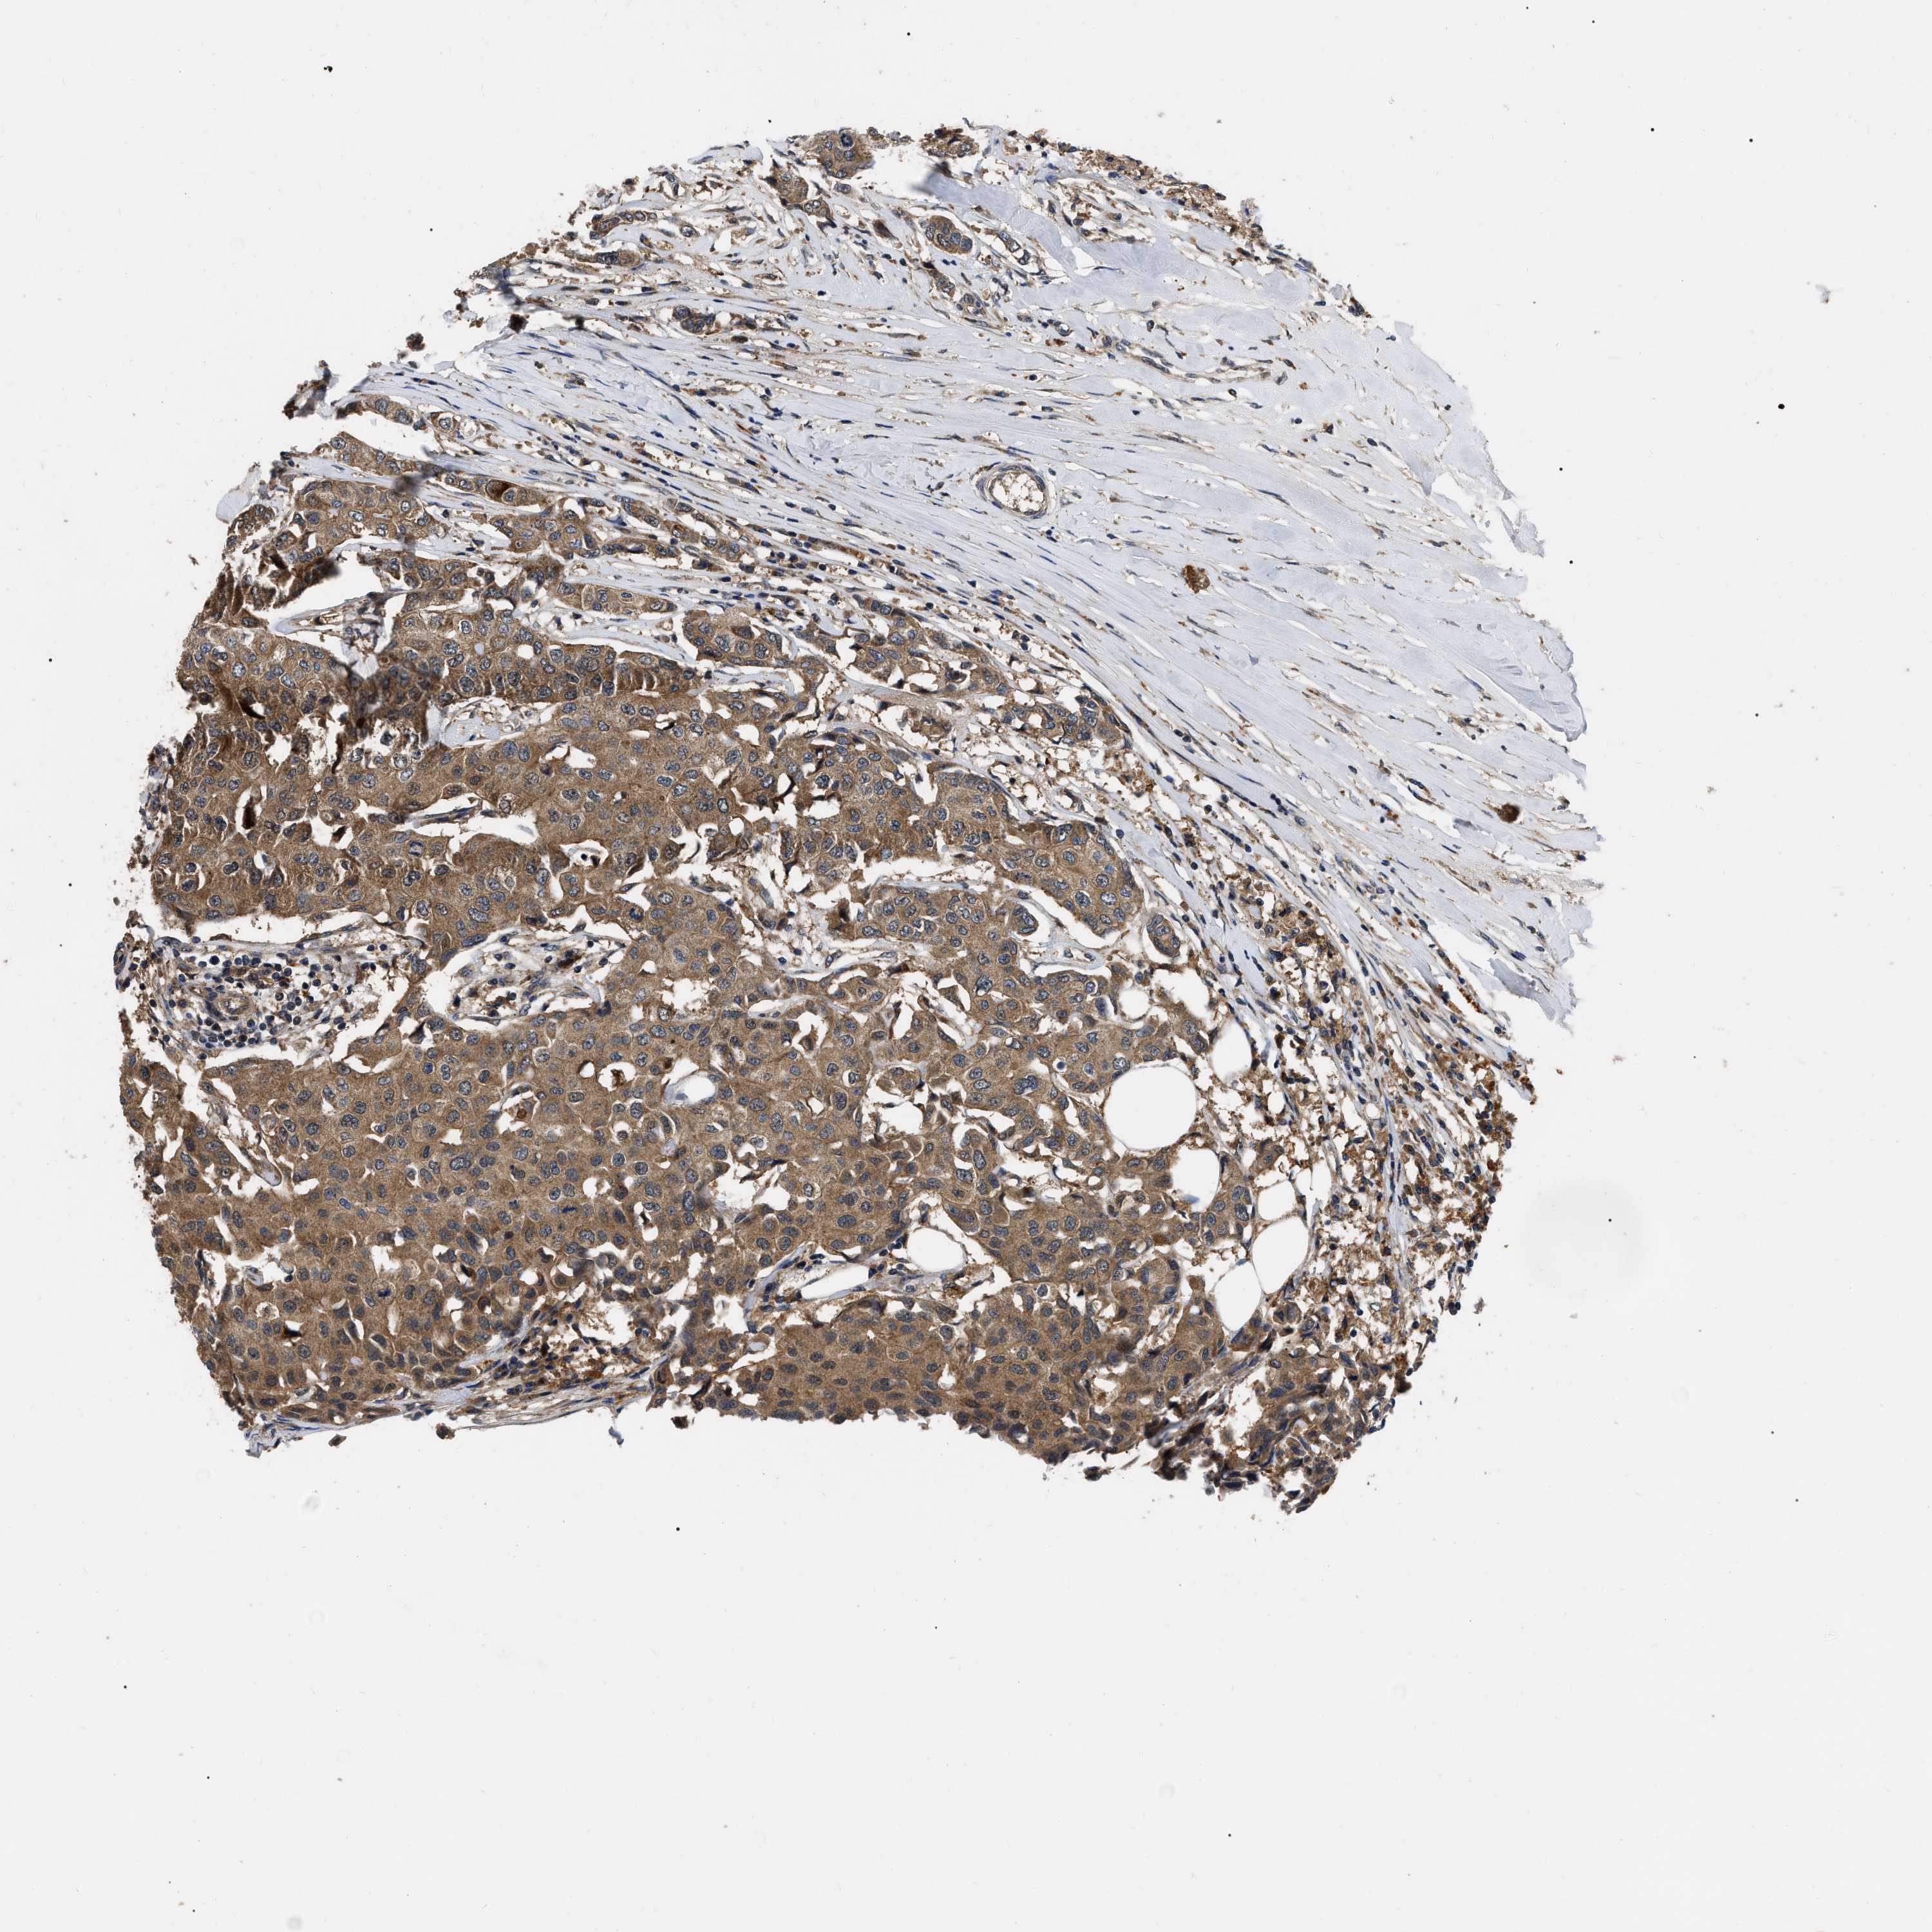

CANCER BREAST CANCER Show tissue menu

BRCA TCGA BRCA VALIDATION PROTEIN EXPRESSION